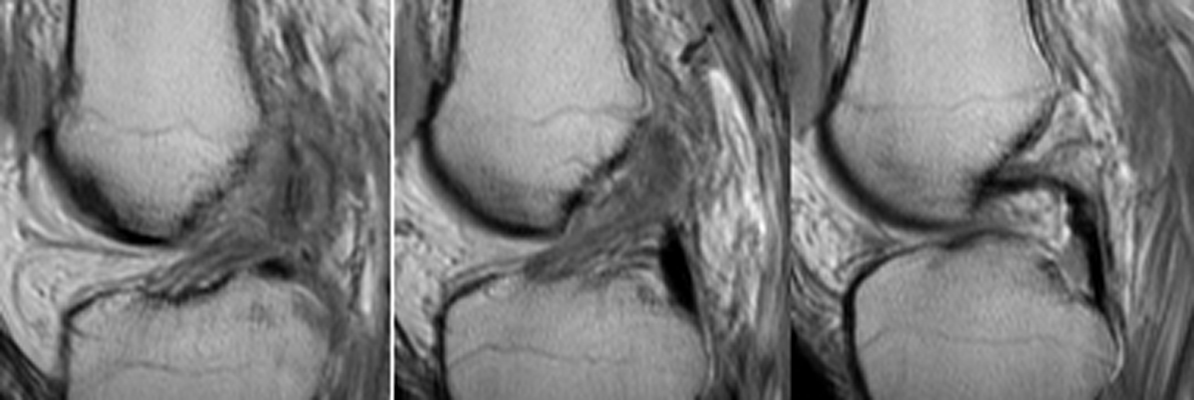

Diagnosis:ACL Tear - Segund fracture Discussion:Frontal radiographs of the knee which reveal a small fleck of bone adjacent to the lateral aspect of the lateral tibial plateau. This "lateral capsular sign" is a simple radiographic finding visible on the routine AP knee x-ray, which indicates severe lateral capsular injury and should alert the examiner to the possibility of ACL tear. The fleck of bone represents an avulsion of the meniscotibial portion of the middle one-third of the lateral capsular ligament. It most commonly implies a disruption of the capsular ligament and the ACL. A-B Radiographs. C. MRI confirms the diagnosis of ACL tear. References: